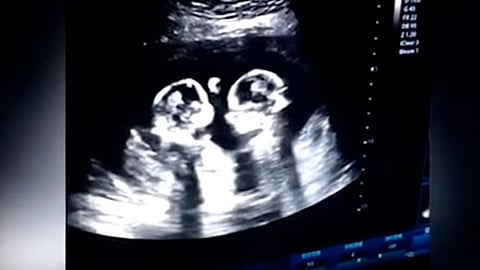

El nombre del hombre es Tao, y este extraño momento fue captado en una ecografía, cuando las gemelas tenían sólo cuatro meses y aunque no se trató en realidad de una pelea, sus movimientos parecen los de Canelo Álvarez y Manny Pacquiao.

Sin embargo, este no es el único momento captado por Tao, quien declaró que unas semanas antes, en otra ecografía, las observaron abrazadas.

Las menores fueron nombradas Cherry y Strawberry y pertenecen a una pequeña cifra de gemelos monoamnióticos monocoriales, conocidos como gemelos Mo-Mo, embarazos riesgosos y extraños, ya que solo hay un 50% de probabilidades de que los bebés sobrevivan después de las 26 semanas.